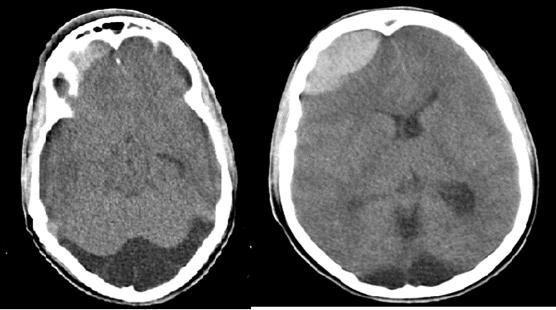

El estudio informó ausencia de línea de fractura; todas las cavidades que conforman los senos paranasales, exceptuando seno esfenoidal, se encontraban prácticamente ocupadas por material hiperdenso de aspecto inflamatorio, con formación de nivel en seno maxilar derecho y varios niveles en senos frontales, evidencias relacionadas con pansinusopatía. Se visualizó, además, proptosis del globo ocular de este lado, con aumento de la grasa alrededor del párpado y de la órbita, acompañado de colección con nivel hidroaéreo en la cara interna de la órbita, a nivel de los tejidos blandos subperiósticos, con erosión de la pared de las celdillas etmoidales contiguas y pared posterolateral derecha del seno frontal, presencia de gas periorbitario y perinasal anterior, con el aspecto de celulitis preseptal y orbitaria con absceso subperióstico y enfisema subcutáneo. A nivel de fosa posterior, fue visible un ensanchamiento del espacio subaracnoideo, con un IV ventrículo normal, por la presencia de una megacisterna magna (Fig. 1 y Fig. 2). En cortes a nivel de la región supratentorial se evidenció ligero borramiento de surcos y circunvoluciones por signos de hipertensión endocraneana (HTE). En la porción anterosuperior de la región frontal derecha se observó, además, imagen hiperdensa, de márgenes bien definidos, convexa hacia el parénquima cerebral, con grosor máximo de 23 mm, sin edema perilesional, la cual provocaba efecto de masa con compresión del asta frontal del sistema ventricular ipsilateral y desplazamiento 9 mm de estructuras de la línea media, por colección epidural (Fig. 3).

Todos estos hallazgos tomográficos condujeron a la siguiente impresión diagnóstica: Colección epidural, signos de HTE, celulitis orbitaria y absceso subperióstico secundarios a pansinusopatía complicada; megacisterna magna. El paciente fue intervenido quirúrgicamente, con evolución clínica favorable, a pesar de la pérdida de visión del ojo afectado.

La TC supone la técnica de imagen de primera elección para diagnosticar una colección intracraneal, por ser un procedimiento rápido, relativamente sencillo, no invasivo y de gran fiabilidad en la mayoría de las ocasiones. Posee también la ventaja de que permite describir con precisión las fracturas óseas, que en muchos casos acompañan a los traumatismos craneales. La TC pierde eficacia diagnóstica en caso de hemorragias muy pequeñas, o cuando afecta a la parte inferior del tronco-encéfalo o a la fosa posterior, donde la RM tiene mayor sensibilidad. Generalmente basta con realizar una TC de cráneo sin contraste intravenoso. Los HE suelen presentar una morfología de masa hiperdensa biconvexa, con límites bien definidos y que se dispone adyacente a la línea de fractura, si la hay. Su localización preferente es la región temporo-parietal, seguida de la frontal y fosa posterior (este último es el sitio habitual cuando la rotura es venosa). El sangrado comprime el parénquima cerebral adyacente, y provoca importante efecto de masa, y con frecuencia puede dar lugar a una herniación cerebral. El sangrado no cruza suturas, pero sí la hoz cerebral (anterior para la colección epidural)16y el tentorio.